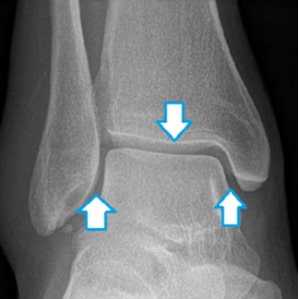

Важно отметить, что рентген применяется не только для определения тех или иных видов переломов, но и с целью выявления повреждений синдесмоза.

Рис. 8 Форма вилки голеностопа полностью соответствует форме таранной кости. При этом, ширина щели сустава (отмечена стрелками) одинакова с каждой стороны.

На рентгенограмме в переднее-задней проекции основными проявлениями недостаточности синдесмоза являются расширение вилки голеностопного сустава, расширение медиальной суставной щели и наклон таранной кости во фронтальной плоскости, травматическая эрозия плафона большеберцовой кости. Задний вывих малоберцовой кости в дистальной части голени виден, как заднее смещение малоберцовой кости относительно большеберцовой кости. Делают рентгенограммы с внутренней и наружной ротацией голени на которых имеется асимметрия суставной щели, расширение вилки голеностопного сустава, смещение наружной лодыжки назад и наклон таранной кости. Синдесмоз может оказаться поврежденным при отсутствии рентгенологических изменений. Самым информативным методом, который позволяет рассмотреть состояние отдельных связок, выявить дефект синдесмоза и определить соотношение костей голени является МРТ.